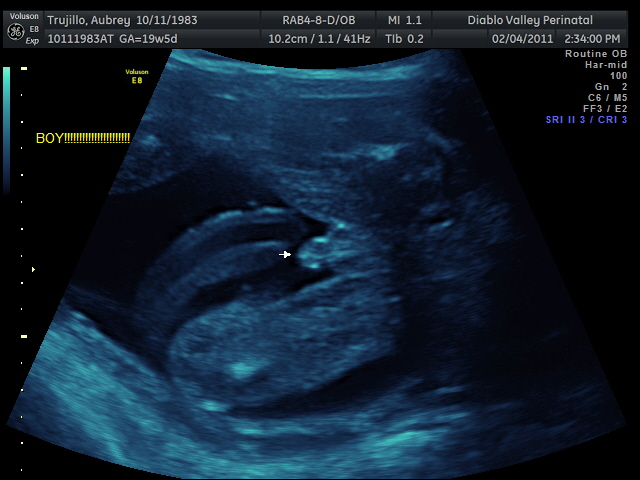

20 weeks - profile20 weeks - Profile again20 weeks - Right foot!20 weeks - sucking thumb!!!!20 weeks - hand near face20 weeks - flexing his bony arms!20 weeks - hiding from mommy and daddy!20 weeks - it's a boy!33 weeks - 3D!33 weeks - 3D!33 weeks - 3D!